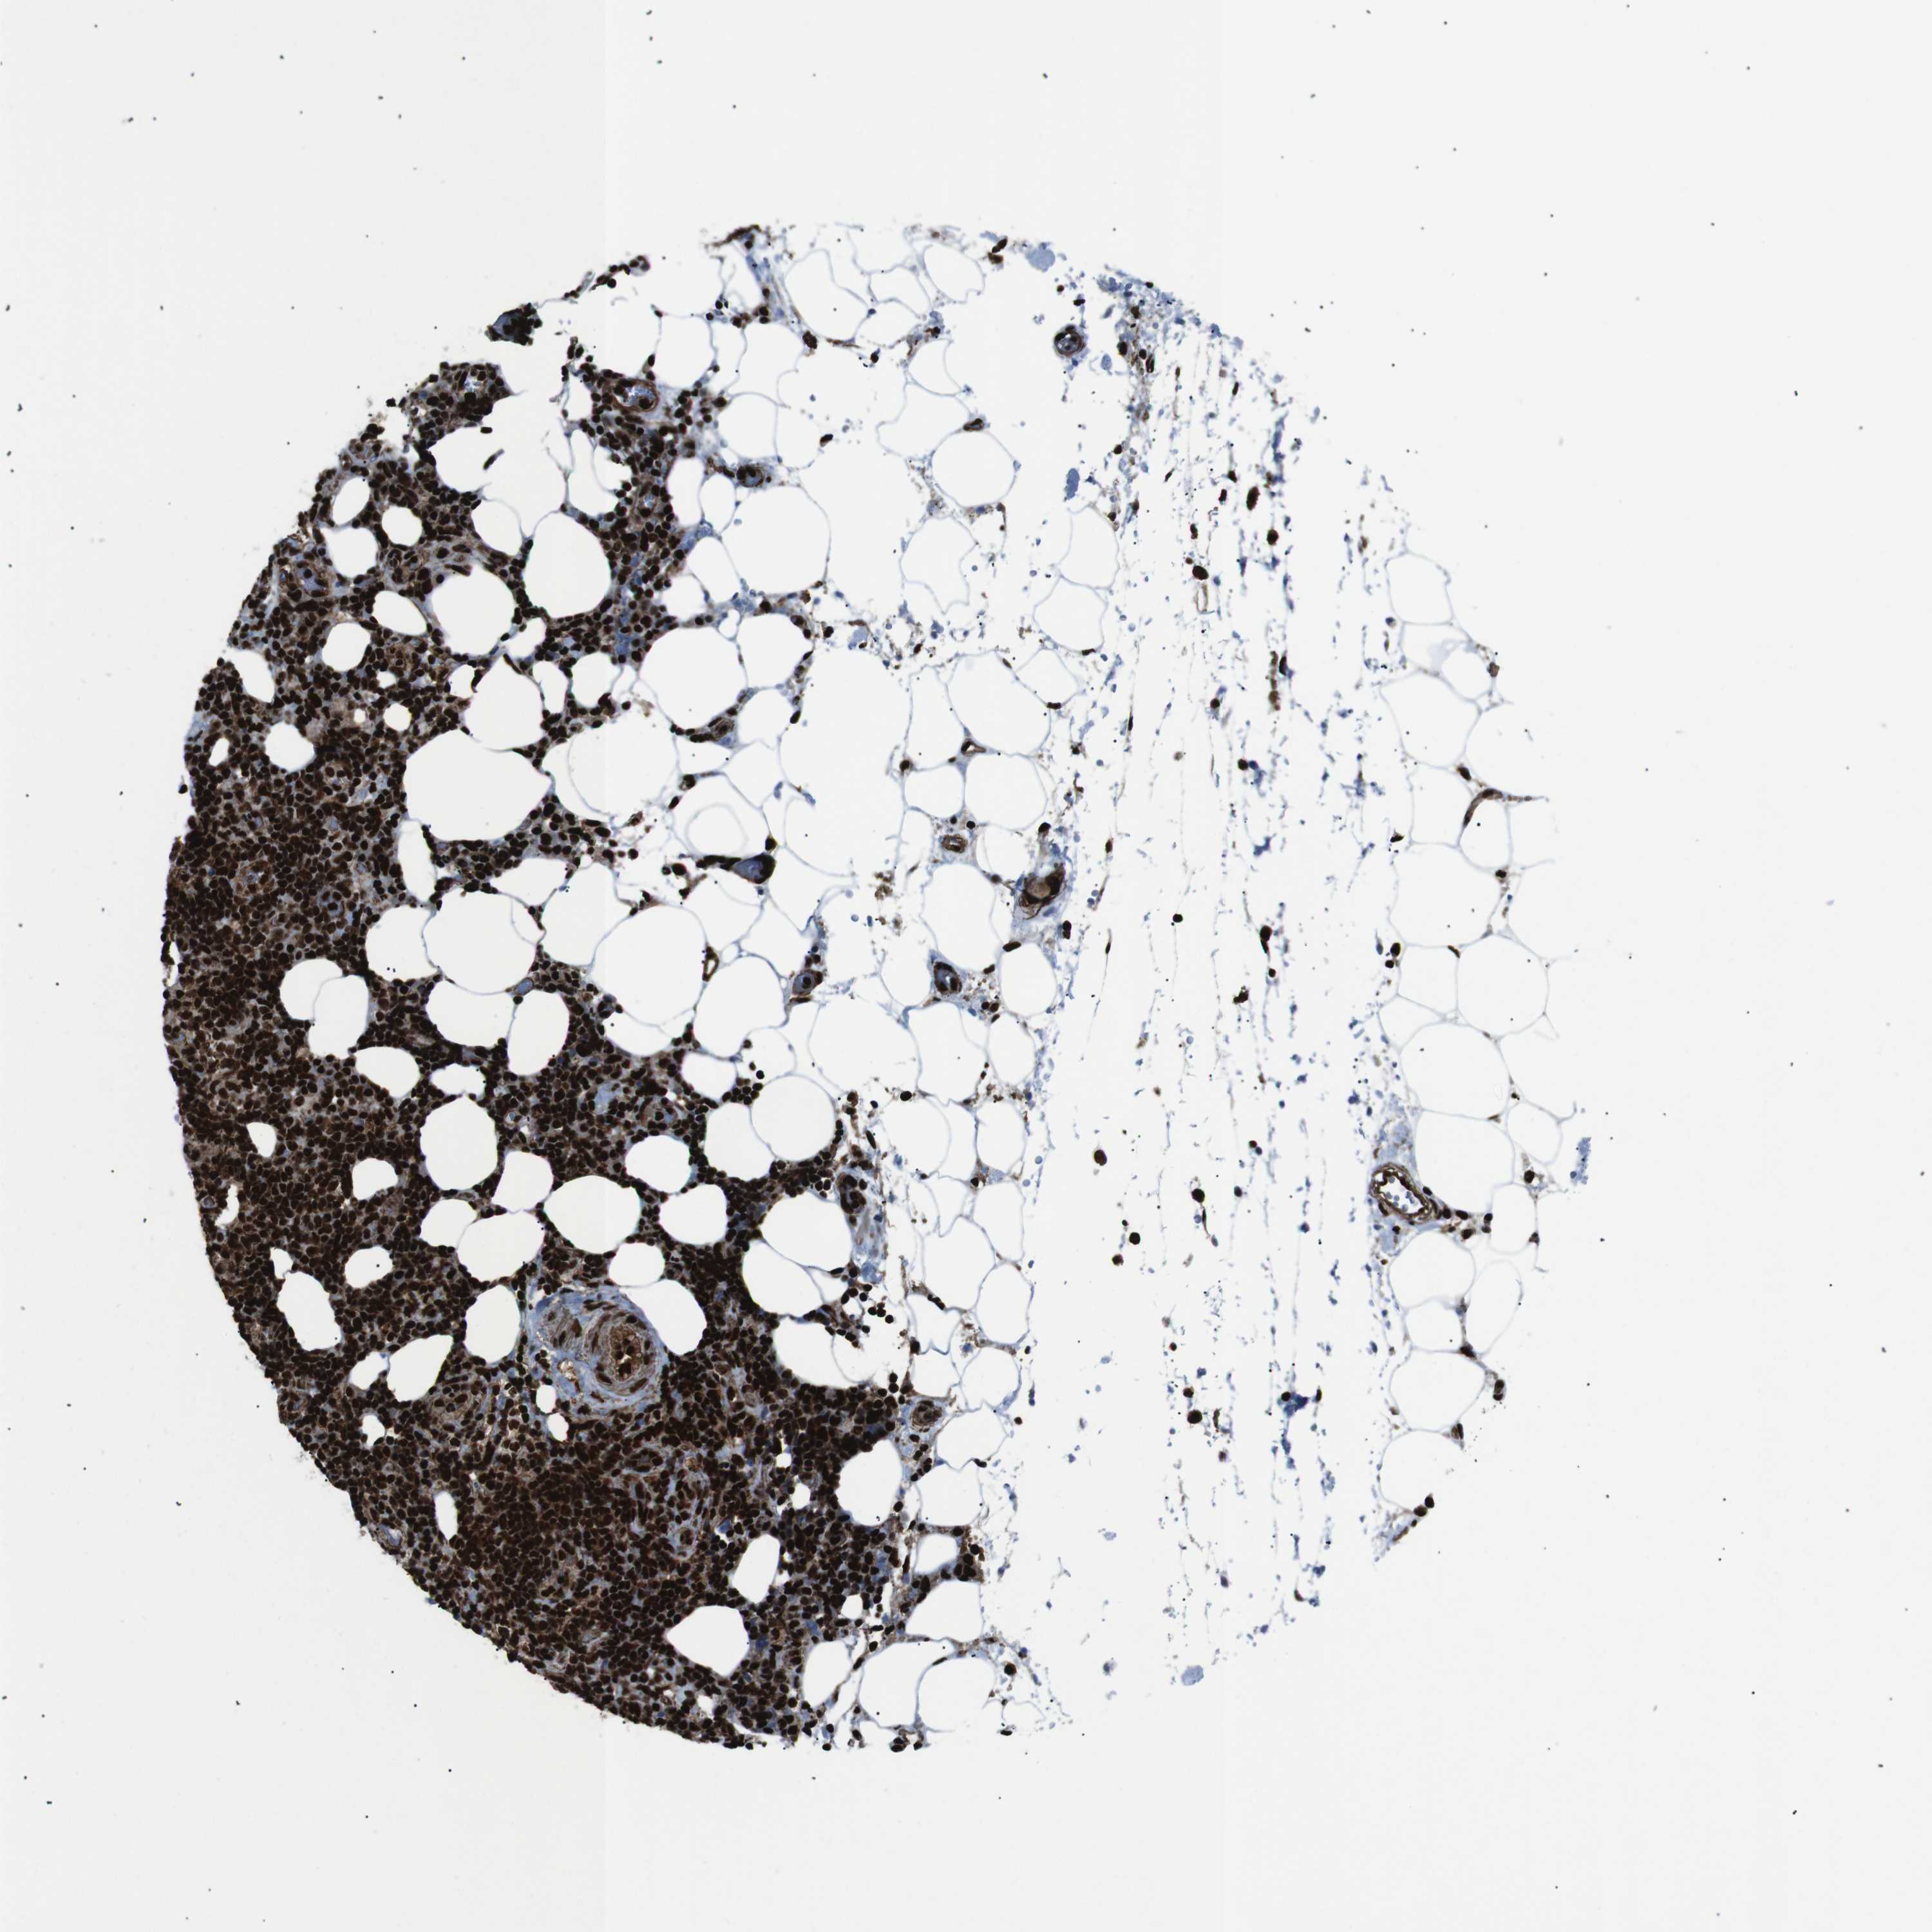

CANCER LYMPHOMA Show tissue menu

LYMPHOMA - Protein expressioni

A mouse-over function shows sample information and annotation data. Click on an image to view it in a full screen mode. Samples can be filtered based on level of antibody staining by selecting one or several of the following categories: high, medium, low and not detected. The assay and annotation is described here.

Each image is clickable and will lead to virtual microscopy that enables deeper exploration of all samples and also displays staining intensity scores, fraction scores and subcellular localization as well as patient and tissue information for each sample.

Antibody HPA041057

Antibody HPA058707

Antibody CAB011532

Malignant lymphoma, non-Hodgkin's type, Low grade

Malignant lymphoma, non-Hodgkin's type, High grade

Hodgkin's disease, NOS